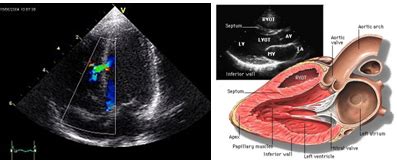

Systolic Function Echo

Systolic Function Echocardiography

Echo Assessment of Systolic Function